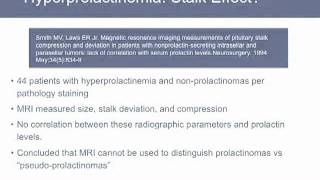

Post-Operative Course - Cushings Remission | UCLA Pituitary Tumor Program Discussion - Stalk Effect | UCLA Pituitary Tumor Program

Discussion - Stalk Effect | UCLA Pituitary Tumor Program

Post-Operative Course - Cushings Remission | UCLA Pituitary Tumor Program Discussion - Stalk Effect | UCLA Pituitary Tumor Program

Discussion - Stalk Effect | UCLA Pituitary Tumor Program